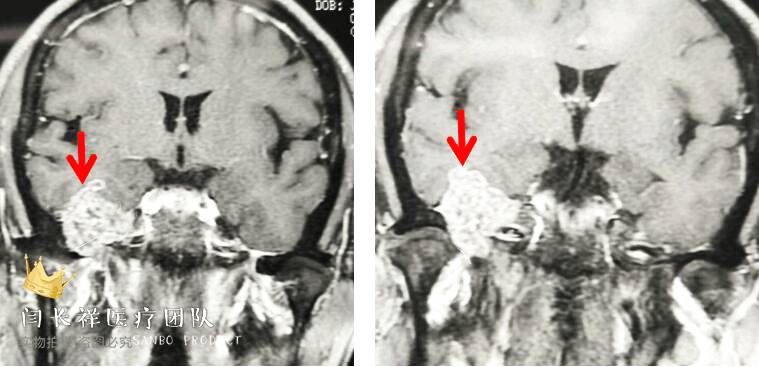

术前MRI轴位T1扫描示病灶呈等信号。

术前MRI轴位T2扫描示病灶侵及面神经膝段及中耳骨质。

术前MRI轴位T1增强示病灶显著不均匀强化。